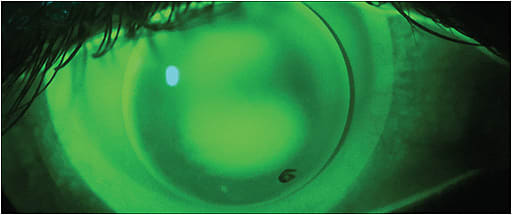

Once the lenses are on the eye, assessment of the fit does not change. The fluorescein pattern, centration, and movement should all be assessed. An alignment-fit GP is the general goal (Figure 1). If the soft lens does not center well over the cornea, the GP may become unstable and also decenter. A steeper base curve soft lens may help.